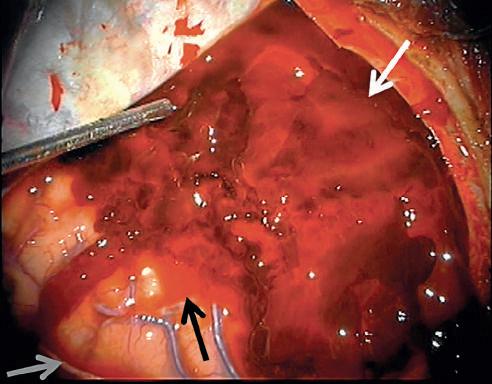

Figure 2.5. Intraoperative photograph of craniotomy for evacuation of an acute subdural hematoma. Notice the large semisolid heterogeneous dark-red subdural blood clot (white arrow) between the overlying folded dura and the underlying brain. The semisolid gelatinous consistency of the acute subdural clot differs from that of the viscous fluid of the unclotted acute blood (black arrow) and from that of the less viscous bloody cerebrospinal fluid evident at the edge of the picture (gray arrow) (Courtesy Dr. Kavian Shahi.)